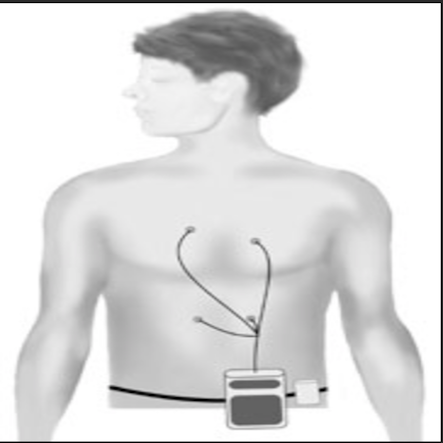

Following clinical assessment, Prof Ruparelia may suggest some investigations to aid reaching a diagnosis and to guide ongoing management. He will always explain what this involves and why they are needed.

Below, please find more information with regards to what the more common investigations entail: